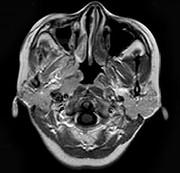

问题 女,34岁。右侧听力下降,耳鸣2个月。MRI平扫及增强扫描如图示,最可能的诊断是()

选项 A.鼻咽癌 B.脑膜瘤 C.神经源性肿瘤 D.动脉瘤 E.未见异常

答案 A